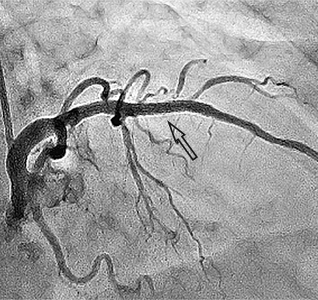

Ангіограми стентування лівої коронарної артерії:

стеноз лівої коронарної артерії    stent    відновлення отвору коронарної артерії

Критичний стеноз лівої коронарної артерії   Розправлений стент    Просвіт артерії відновлено